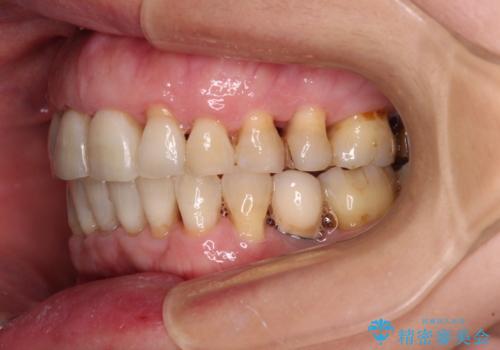

- 近医にてインプラント治療を行った後に矯正治療を希望され、来院された患者様です。

口元の突出感とデコボコが気になっているとのことでしたが、インプラントが既に3本埋入されていたため、抜歯矯正による口元を引っ込めることができない状況でした。

近医での歯周病治療の影響でブラックトライアングルが発現していたため、IPR(歯と歯の間を削る)で隙間を改善しつつ、インプラントを固定源に歯列全体を後方へ移動させることとしました。

インプラントは矯正治療では動かすことができないため、インプラント治療を行う前に矯正治療を行う意思があるのかを確認します。

特に出っ歯などで抜歯矯正となる場合には、インプラントが邪魔になることがあるので注意する必要があります。